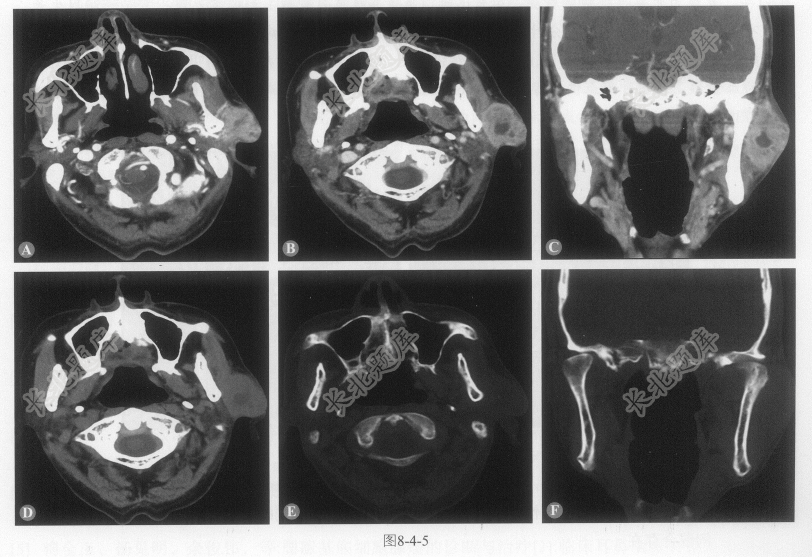

[材料题] 患者男性,86岁,发现左耳前包块1年,质地较硬。CT图像如图8-4-5(病灶实性成分CT值:平扫38~40HU、动脉期76~101HU、静脉期85~98HU、延迟期80~85HU)。

A、左侧腮腺浅叶一不规则肿块影,呈分叶状

B、病灶部分边界不清,其内散在液性低密度影

C、增强扫描呈明显不均匀强化,液性部分无强化

D、病灶与邻近咬肌分界不清

E、邻近下颌骨骨质破坏